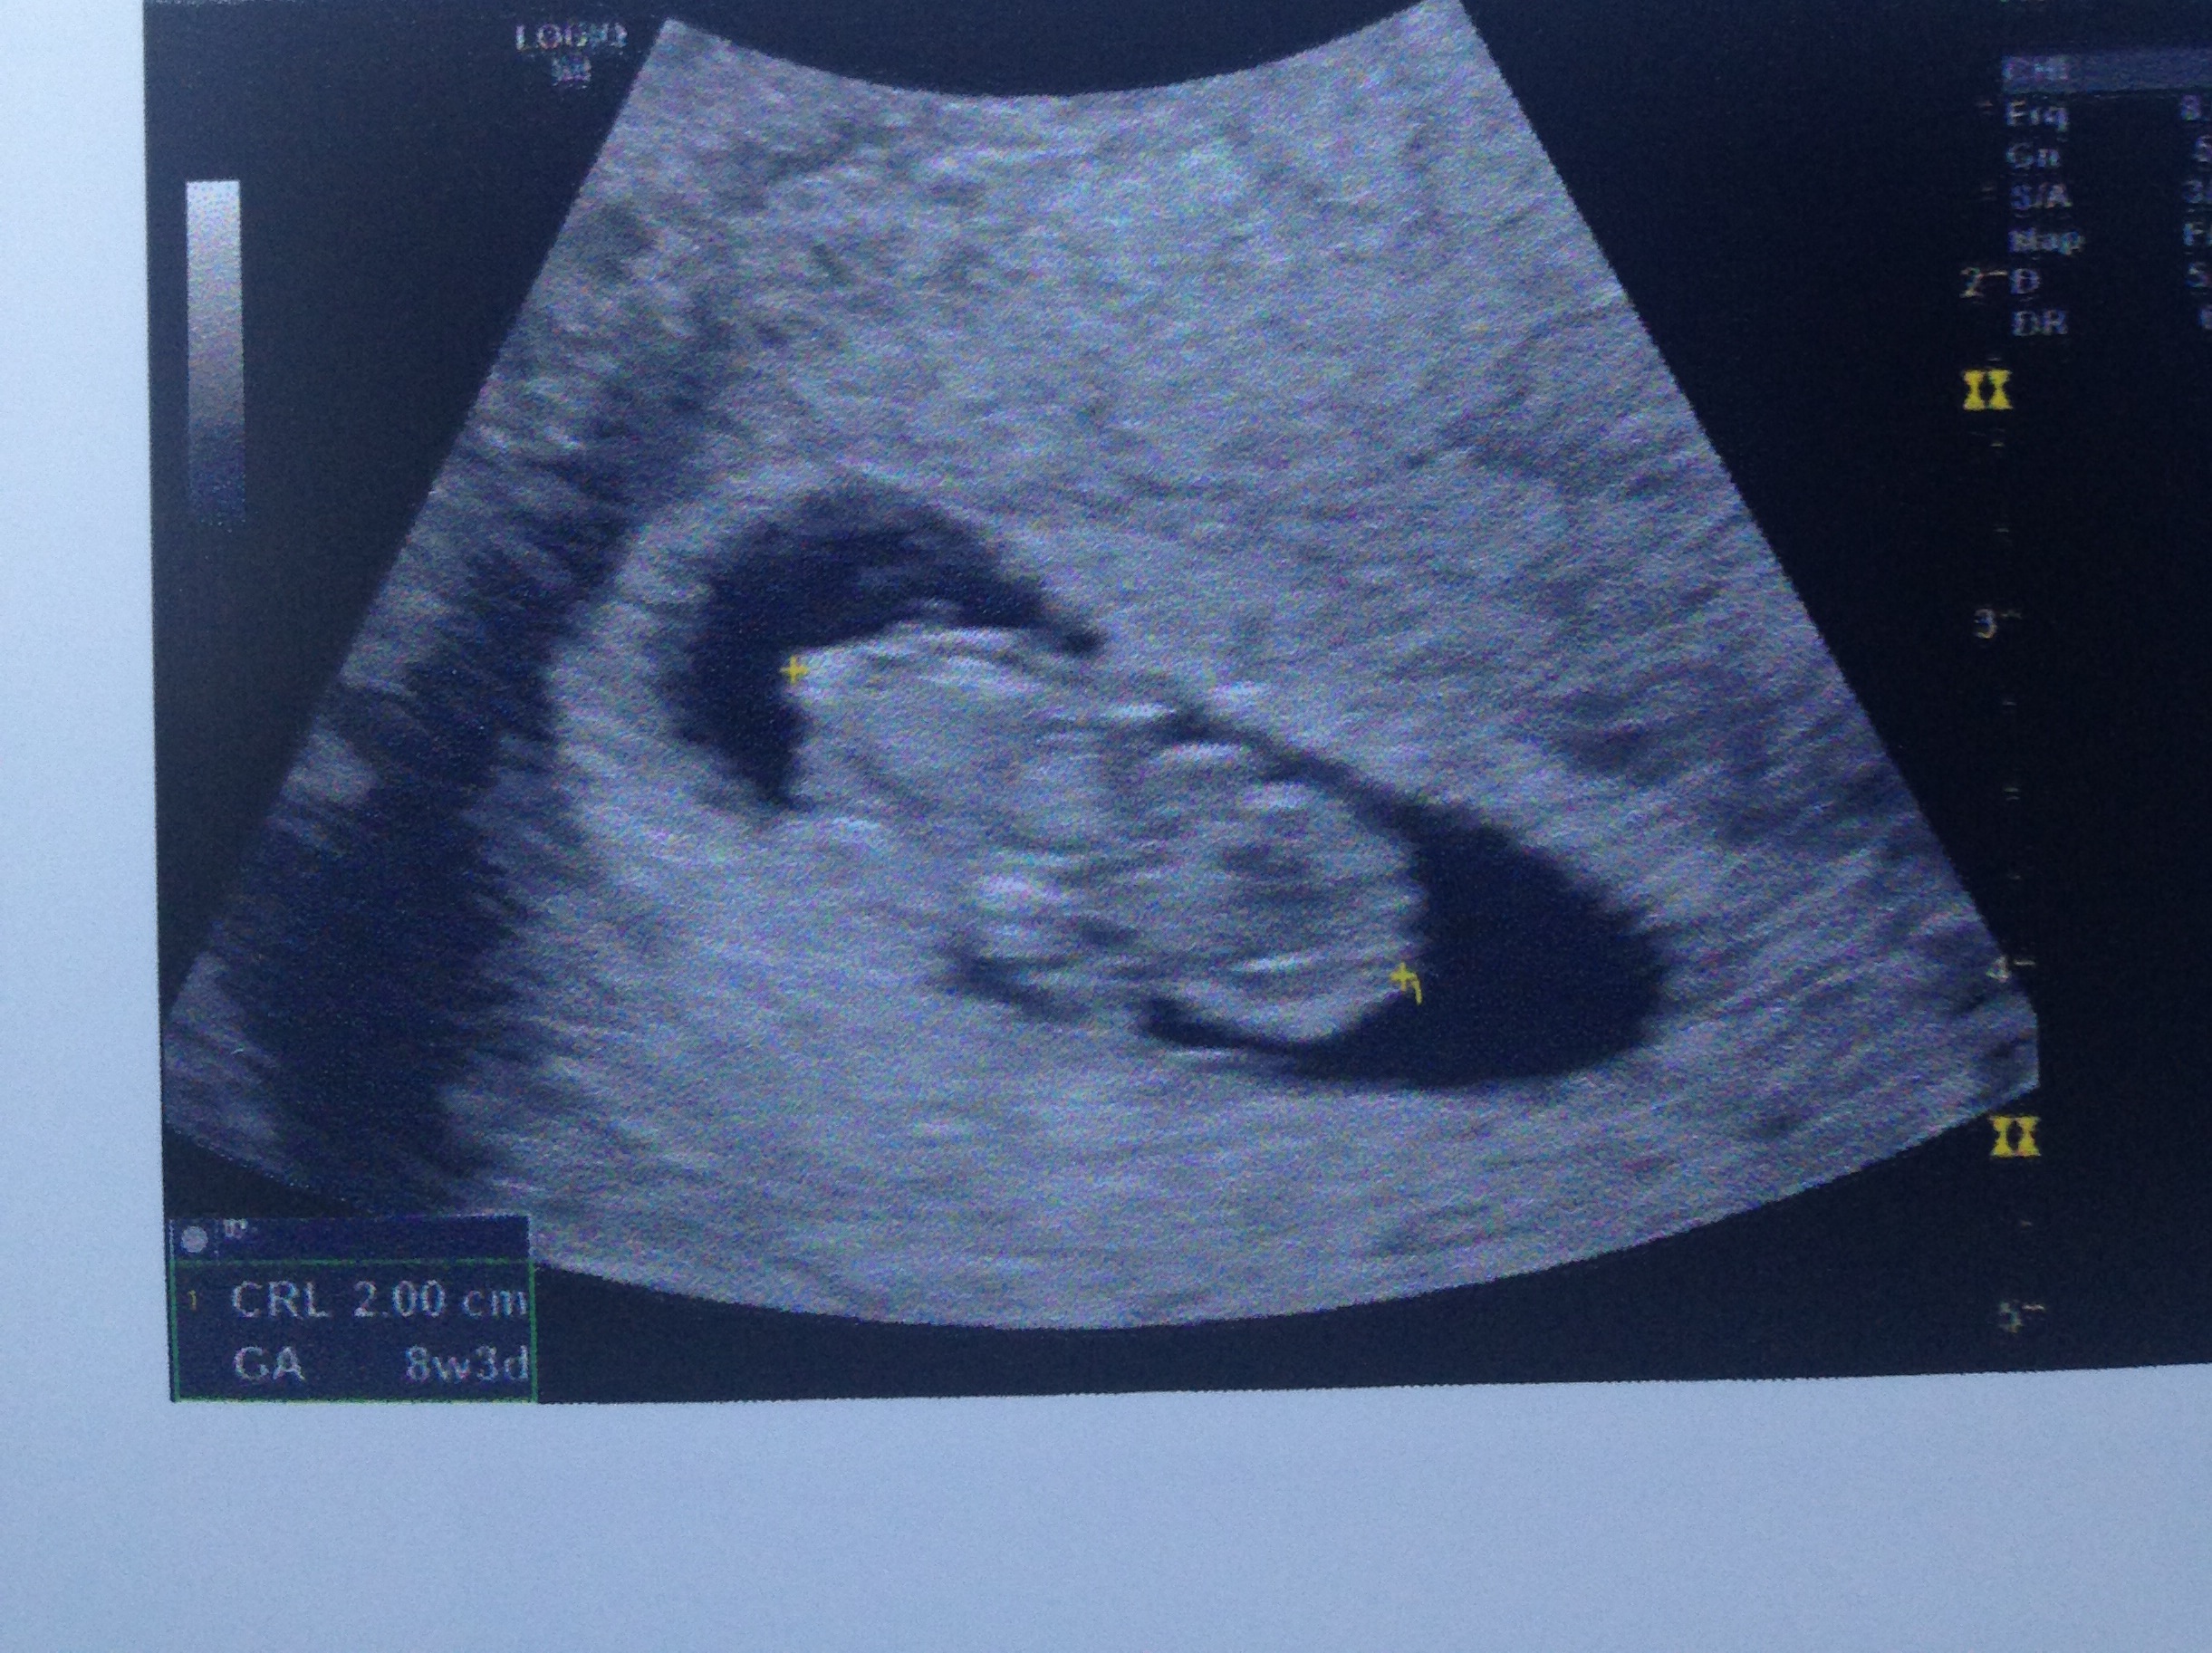

So today I started spotting at work which I know isn't a big deal but for me I've had 3 previous losses and they all started out with slight pink spotting which is what I had today. So as worried as I was I left work and went straight to the GP thank goodness she saw me without an appointment and the didn't even charge me! (I normally pay $85 to see her) she rang a ultrasound place to see if they could fit me in and they managed to squeeze me in, I went in expecting to see no heartbeat and be given bad news cause this is the same week I lost my last baby ( 8 weeks 3 days) I went straight in and straight away there was baby with a heartbeat of 176 and measuring exactly on track! I was expecting to just see a big blob but it actually kind of looks like a baby

we could see the head and the arm and leg buds and it even wriggled!! Sorry this is so long but I'm so relived just hopping the spotting stops. He couldn't find a reason for it so that's good.